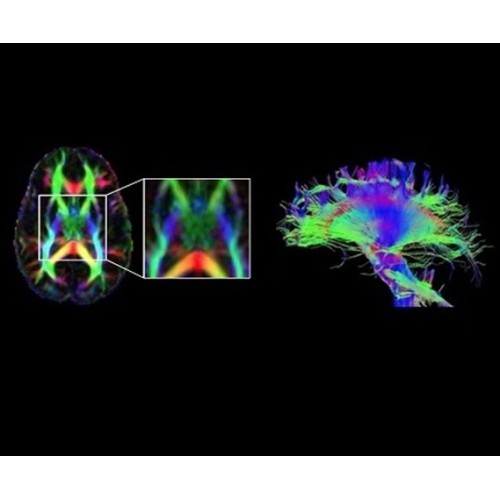

• Специальный пакет приложений для измерения и сравнения объемных изображений ЦНС с нормами поможет вам в диагностике нейродегенеративных заболеваний, а дополнительные инструменты визуализации — в постановке точного диагноза с помощью бета-амилоидов и радиоизотопных маркеров ФДГ.

• In vivo лаборатория — получайте полные данные биохимических процессов in vivo с мультиядерной спектроскопией на SIGNA PET/MR.